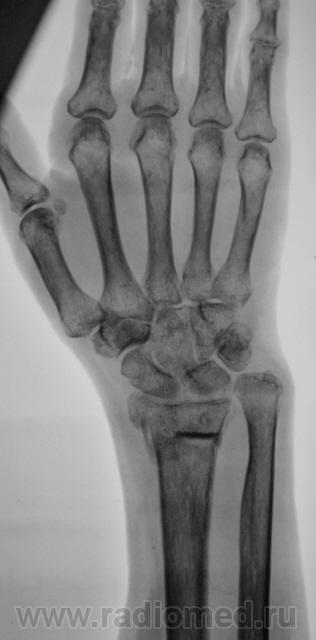

Фрагменты с увеличением.

Пусть интересуется... Гипс снят рановато, стояние отломков - неудовлетворительно,хотя бывает и хуже

Если срок сращения 4 недели, то признаки консолидации выражены соответственно сроку достаточно хорошо. Перелом компрессионный, поэтому произошел вывих в л/л суставе. Можно или нет его было устранить в амбулаторных условиях - судить не берусь. Осколок кортикала в луче "захряснет", может, рассосется - ничего страшного.

неприятная ситуация(особенно если не было первичной репозиции) есть оппределенные правила ведения таких переломов, первичный снимок, сразу после репозиции, через 4-5 дней после репозиции и если нет вторичного смещения в гипсе то через 4-5 недель уже без гипса. ситуация на данный момент спорная, лучше наложить аппарат Илизарова для дальнейшей иммобилизации и профилактики контрактуры л\зап сустава. если возраст пациентки почтенный, то гипсовая иммобилизация доолжна быть продлена до 8 недель.